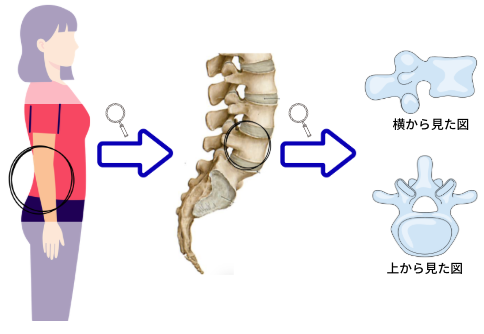

僕らの背骨は腰から首までS字にカーブしながら繋がり、重い頭を支えています。腰の骨は専門的には“腰椎”というのですが、腰椎の形はこのように、四角いブロックに羽が生えたような形をしています。

この腰のブロックは全部で5つあり、下から順番に5番目・4番目…と積み上げられ、間にはクッション(椎間板)が挟まっています。そして、それぞれがズレないように、羽が噛み合って固定されています。